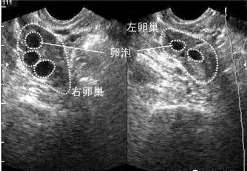

查看全文孕前检查花费并不高!10个项目就能为好孕保驾护航,孕前体检规避风险 孕前检查是备孕前做的一项关于怀孕风险的检测 […]